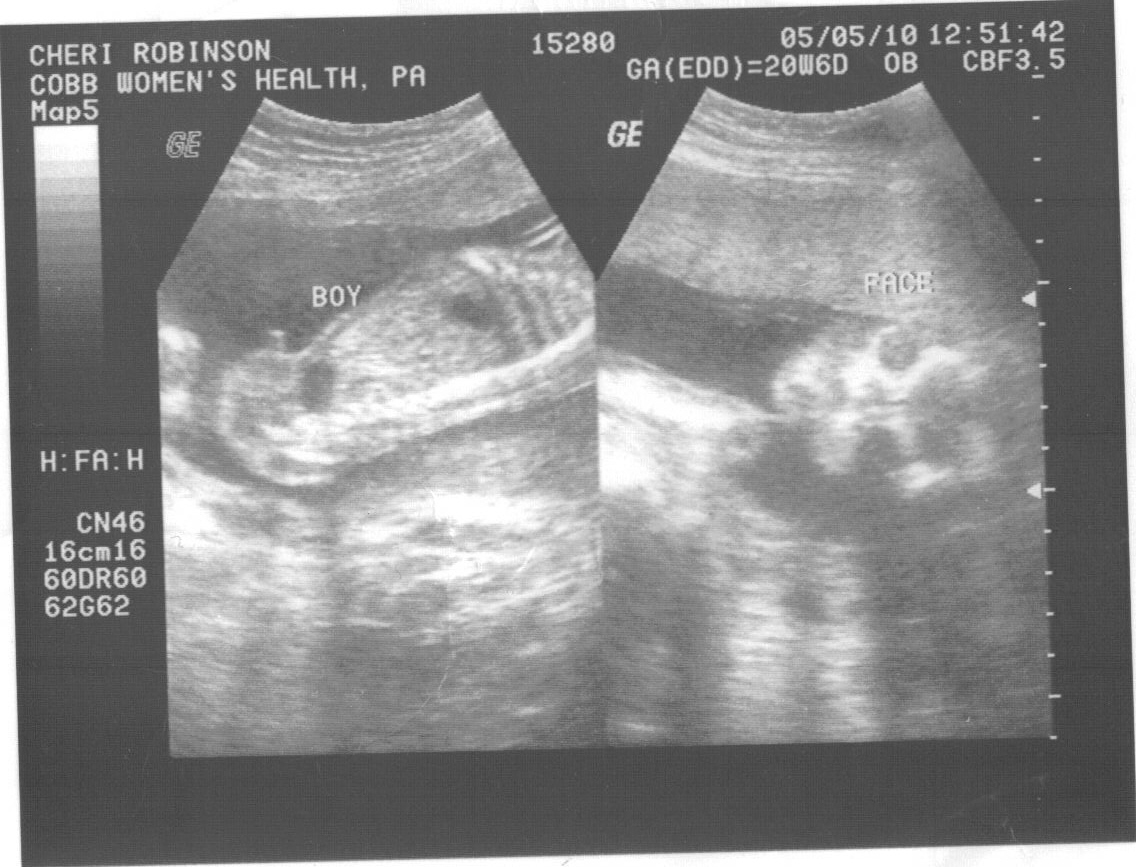

We found out this past Wednesday that a 3rd little boy will be joining our family in September. We are excited and glad that he is perfect and healthy so far! We are thinking of names, but not sure yet...will keep you posted! I will be 22 weeks this Thursday, so in about 18 weeks we will get meet our new little guy, can't wait!

I hadn't seen the ultrasound pics yet & he does have long legs!!!! WoW!! I can't wait to meet him. :)